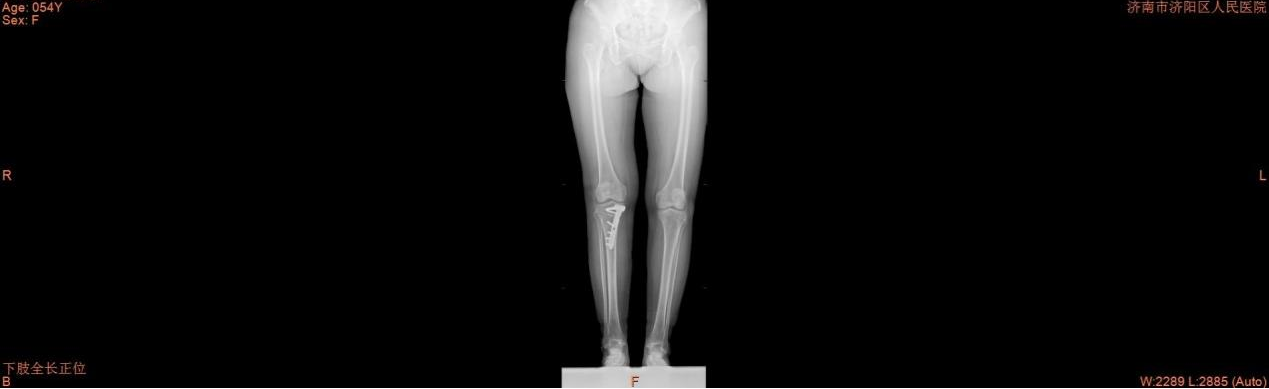

术后

2月20日,手术顺利进行,术中关节镜入路见内侧间隙变窄,半月板撕裂,行半月板成形术。再行胫骨高位截骨,术中模拟外翻负重位状态,透视见下肢力线恢复至正常力线,予以钢板固定植骨术。术后,患者恢复良好,内侧间室疼痛明显减轻,顺利出院。